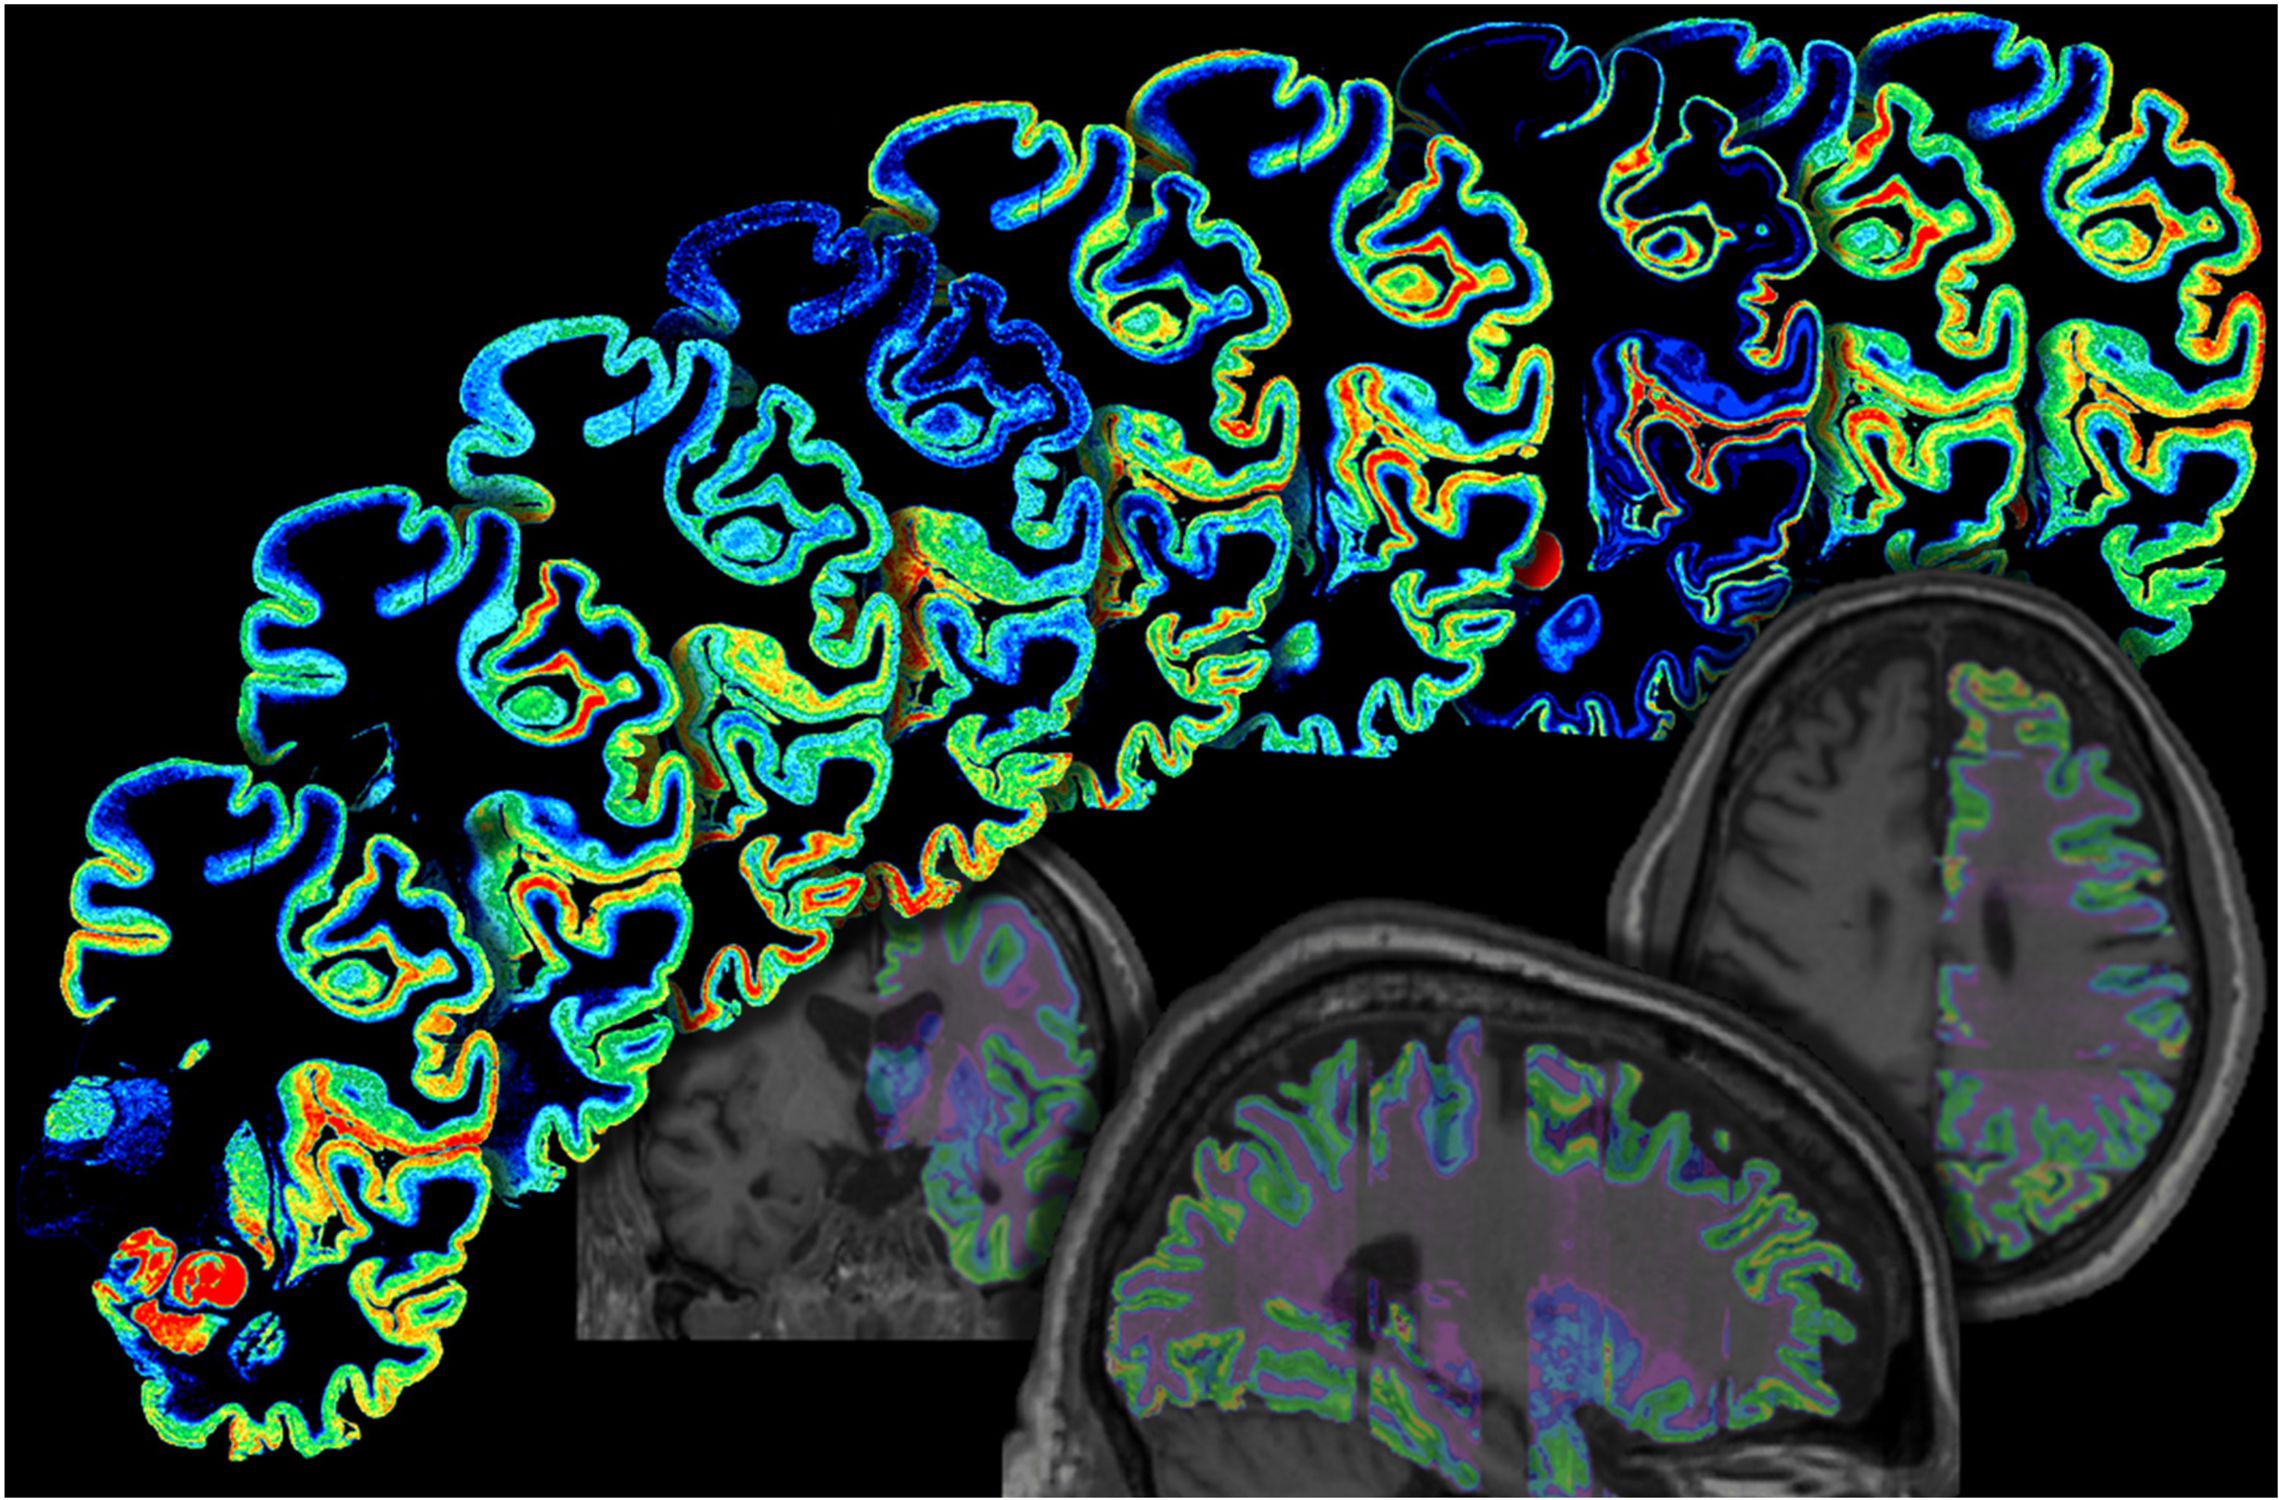

The institute division of Structural and Functional Organization of the Brain (INM-1) is developing a three-dimensional digital atlas of the human brain. For this purpose, areas of the cerebral cortex, subcortical core areas, as well as fiber webs in post-mortem brains are mapped. In order to do justice to the enormous complexity of the human brain, our approach consists in the integration of cyto- and receptorarchitectural, genetic and functional as well as PLI-based maps into a multi-modal atlas of the brain. For this purpose, we develop methods for image analysis and 3D reconstruction, artificial neural networks and big-data analysis with supercomputing.

The „BigBrain“, an ultra-high resolution brain model, and the Julich-Brain, a cytoarchitectural atlas reflecting variations in brain structure, are results of our research.We make our brain maps available to the scientific community. They are part of the HBP Human Brain Atlas and can be merged with neuroimaging data via the Anatomy Toolbox.